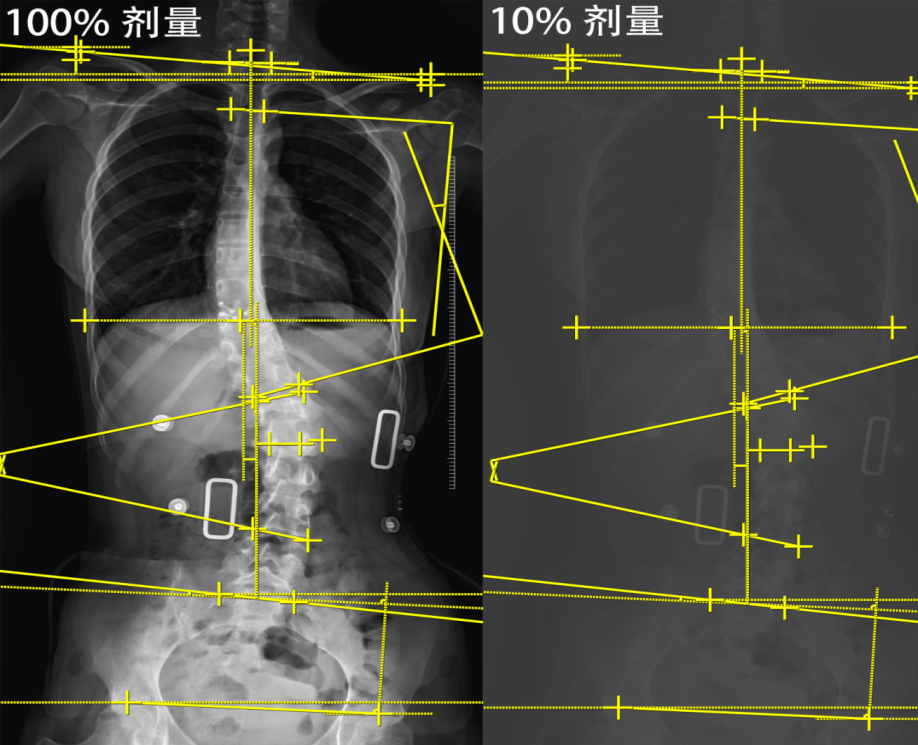

更令人欣喜的是,人工智能(AI)技术也开始应用于这个领域。您可以把它想象成一位不知疲倦的“超级医生助理”。即使是在低剂量拍摄的,甚至略显模糊的X线片上,AI也能精准地找到脊柱的位置,准确测量出Cobb角。它不会疲劳,不会分心,每次都能提供稳定、可靠的测量结果。

图4 版权图片 不授权转载

AI的作用还不止于此。它还能帮助医生预测侧弯的发展趋势,通过分析孩子的一系列X线片,结合年龄、生长发育情况等信息全部读取并分析,给出个性化的建议。这意味着您的孩子能够得到更加精准的治疗方案。

总之,现在的低剂量拍摄技术加上AI辅助诊断,让脊柱侧弯的复查既安全又准确。作为家长,您可以放心地带孩子接受必要的检查,因为现代医学技术已经在很大程度上保护了孩子的健康。